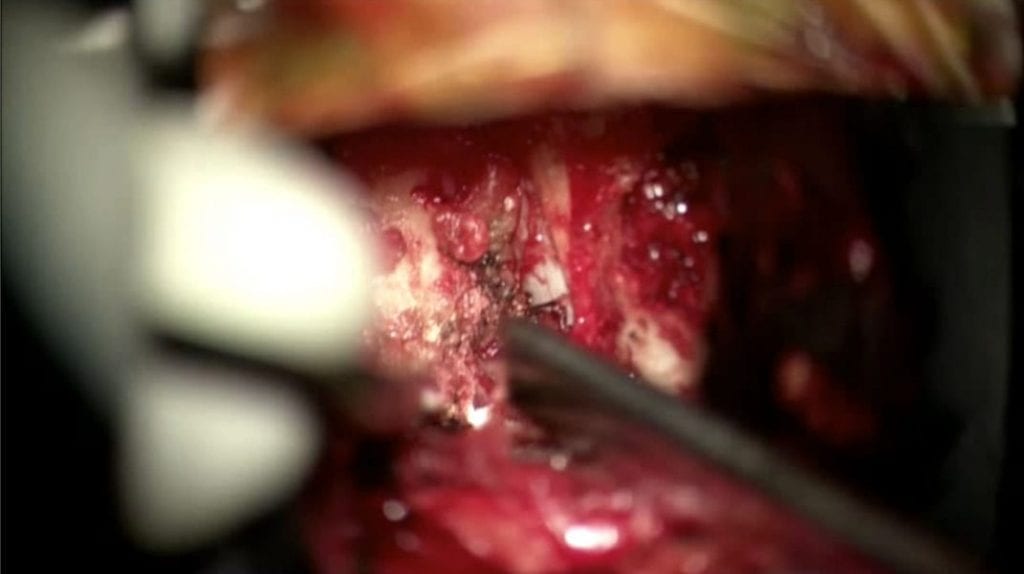

This patient with Trigeminal Neuralgia had surgery in 2012 by another surgeon at another institution. Initially, she felt well, but the pain gradually returned over…